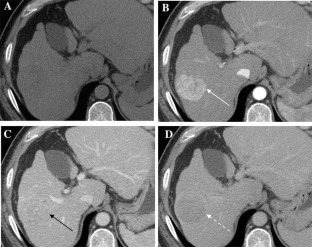

The Liver Imaging Reporting and Data System (LI-RADS) was designed to standardize the interpretation and reporting of observations seen on studies performed in patients at risk for development of hepatocellular carcinoma (HCC). The LI-RADS algorithm guides radiologists through the process of categorizing observations on a spectrum from definitely benign to definitely HCC. Major features are the imaging features used to categorize observations as LI-RADS 3 (intermediate probability of malignancy), LIRADS 4 (probably HCC), and LI-RADS 5 (definite HCC). Major features include arterial phase hyperenhancement, washout appearance, enhancing capsule appearance, size, and threshold growth. Observations that have few major criteria are assigned lower categories than those that have several, with the goal of preserving high specificity for the LR-5 category of Definite HCC. The goal of this paper is to discuss LI-RADS major features, including definitions, rationale for selection as major features, and imaging examples.

Fig. 4